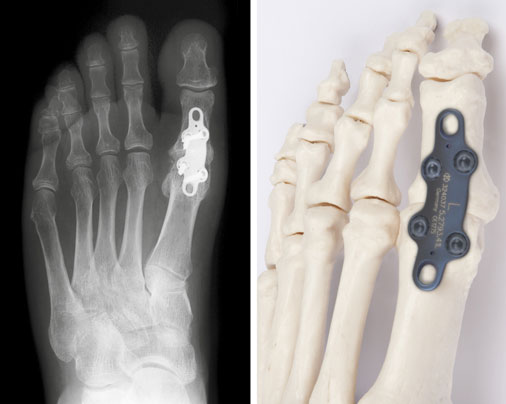

Arthrodese des Großzehengrundgelenks:Hallux rigidus nach Operation im Röntgenbild, rechts das Implantat am Modell

Bei fortgeschrittenen degenerativen Veränderungen bietet sich die Versteifung (Arthrodese) des Großzehengrundgelenks an. Die alternativen Verfahren wie Resektionsinterpositionsarthroplastik (Entfernung der Großzehengrundgliedbasis) und Einbau einer Prothese werden zum jetzigen Zeitpunkt kritisch betrachtet und sollten nur in Ausnahmefällen angewendet werden.